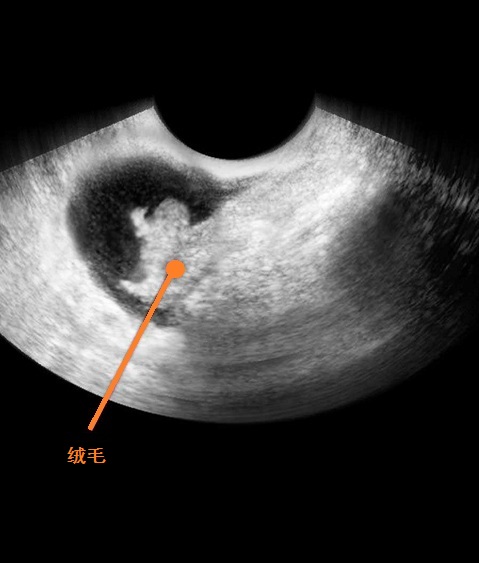

B超图

这一时期,你自身可能还没有什么感觉,但在你的身体内却在进行着一场变革。在最初的几周内,胚胎细胞的发育特快,有三层,称为三胚层。三胚层是胎体发育的始基,每一层都将形成身体的不同器官:最里层形成一条原始管道,它以后发育成肺、肝脏、甲状腺、胰腺、泌尿系统和膀胱。中层将变成骨骼、肌肉、心脏、睾丸或卵巢、肾、脾、血管、血细胞和皮肤的真皮。最外层将形成皮肤、汗腺、乳头、乳房、毛发、指甲、牙釉质和眼的晶状体。